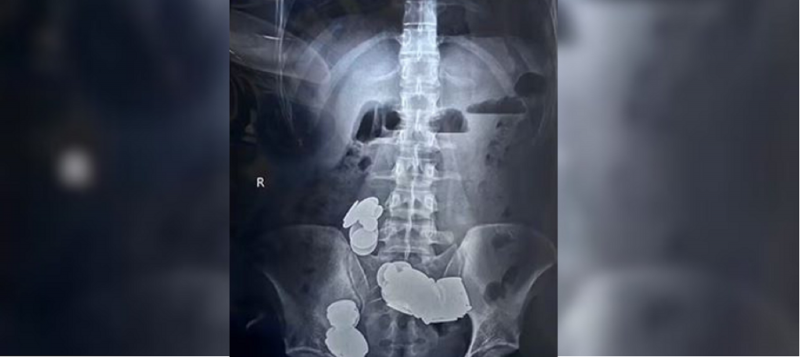

Radiografias prévias à cirurgia realizada no hospital revelaram grandes aglomerados metálicos formando-se nos intestinos do homem. Além disso, o rapaz está recebendo tratamento para uma condição psiquiátrica não especificada.

Os cirurgiões observaram que as moedas e os ímãs agruparam-se em duas alças distintas no intestino delgado, sendo a força magnética responsável por sua aderência e causando erosão na parede intestinal.

A ingestão dos objetos metálicos resultou em obstrução intestinal, exigindo intervenção cirúrgica imediata para remoção.